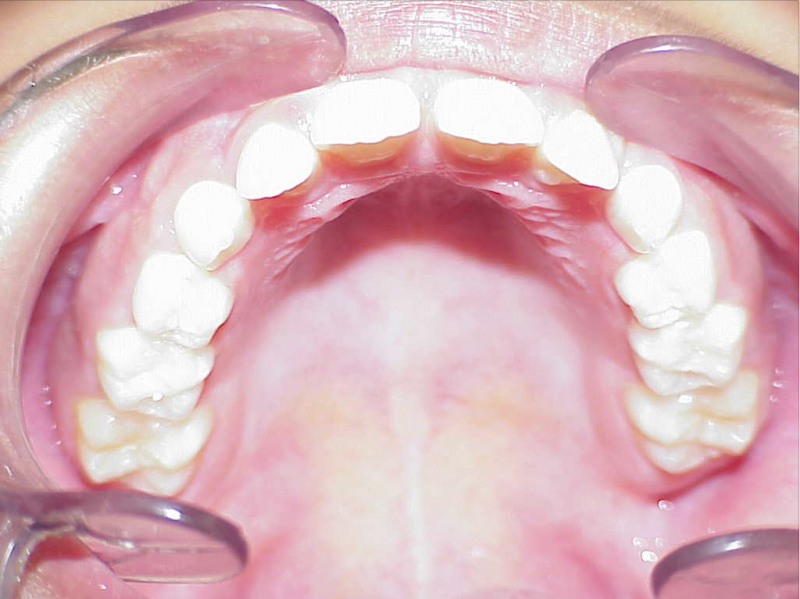

Behandeling Hajar

eindfoto

Beschrijving

Leeftijd bij aanvang: 9 jaar

1-6 maanden Bonded Hyrax in de bovenkaak, banden/slotjes in de onderkaak met Transforce

7-13 maanden: Twinblock

14-47 maanden: Volledig banden/slotjes in de boven-en onderkaak (omdat er hier blijvende kiezen ontbraken moesten er kiezen getrokken worden en de ontstane ruimtes gesloten, dit verklaart de langere behandeltijd)

Retentie fase: Wrap en C-CBar